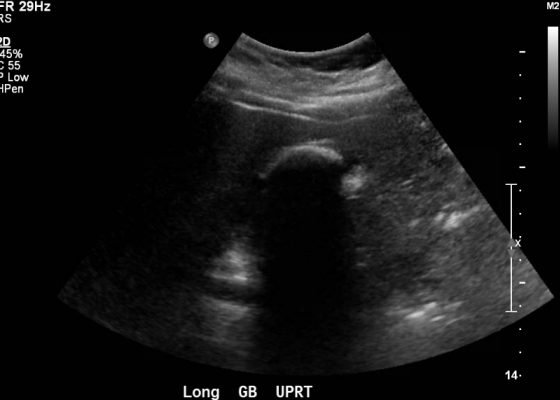

Cholelithiasis: WES Sign

DOI: https://doi.org/10.21980/J8X300Abdominal ultrasound showed the classic presentation of the Wall-Echo-Shadow (WES) sign. The superficial aspect of the gallbladder wall is represented by a hyperechogenic curve. Below this, bile fluid is represented by hypoechogenicity. Underneath the bile fluid is the echo of the dense border created by the collection of gallstones, represented by a hyperechogenic curve. Due to the high density of the gallstones, nothing deeper can be visualized (including other gallstones or the far end of the gallbladder); this is the shadow.